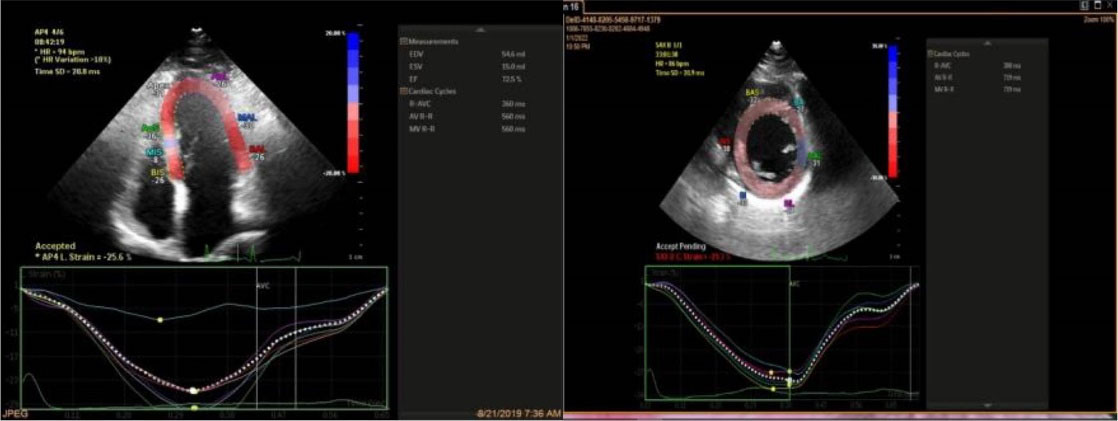

Offline analysis was performed, and strain data were generated. Images used for GLS measurement were obtained in 2-, 3-, and 4- chamber views, and images utilized for GCS calculation were acquired in 3 short-axis views at the basal, mid, and apical levels of the left ventricle (). The gray- scale rate was kept between 30 and 70 frames per second, and electrocardiography was gated. Automated border detection by software underwent subsequent manual correction and resulting calculated GLS and GCS expressed as the bull’s eye ().

Figure 1.

Detection of the endocardial and epicardial border throughout the cardiac cycle (Left: Apical 4 chamber view for global longitudinal strain calculation, right: Parasternal mid ventricular short axis view for global circumferential strain calculation)